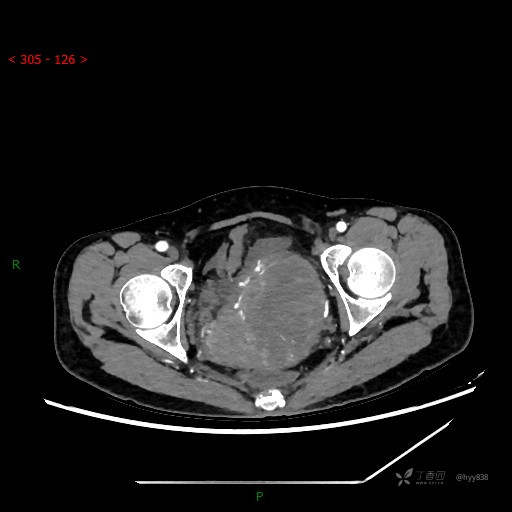

静脉期